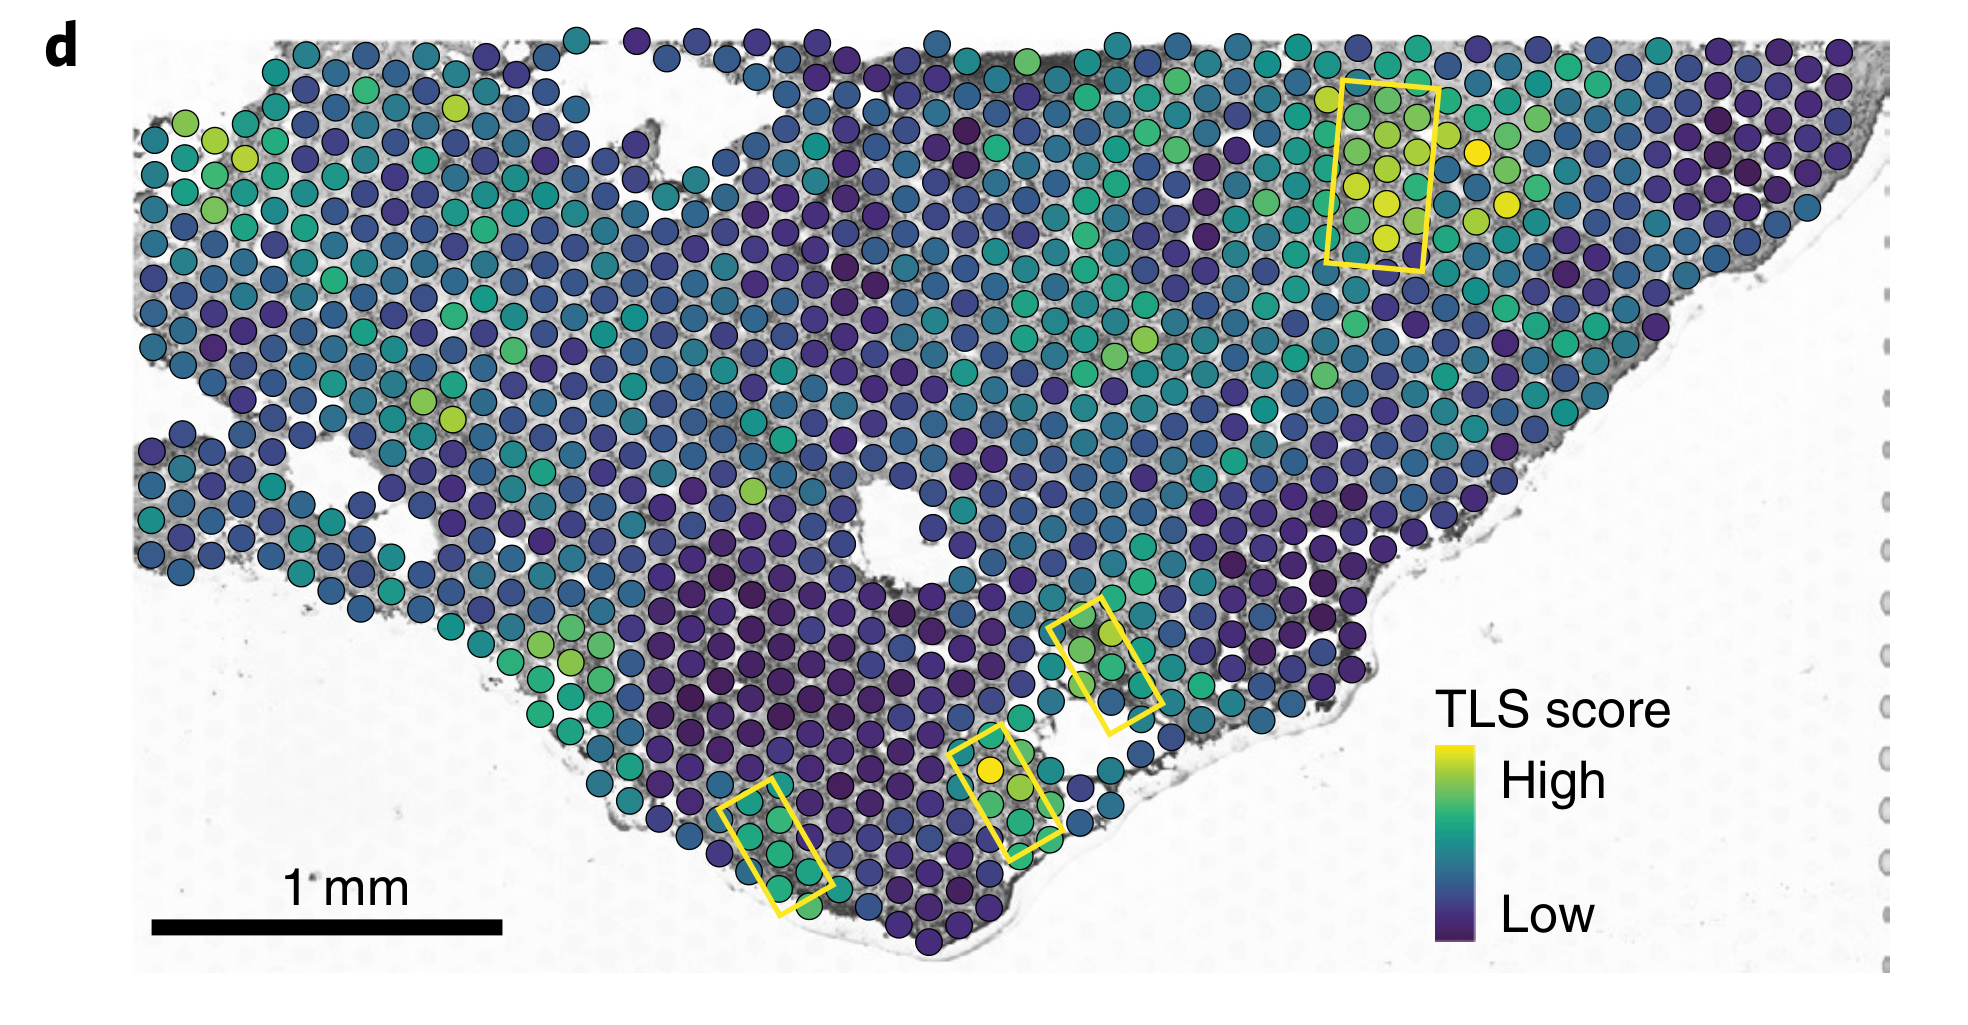

Where in the tissue is a specific transcriptional program spatially active?